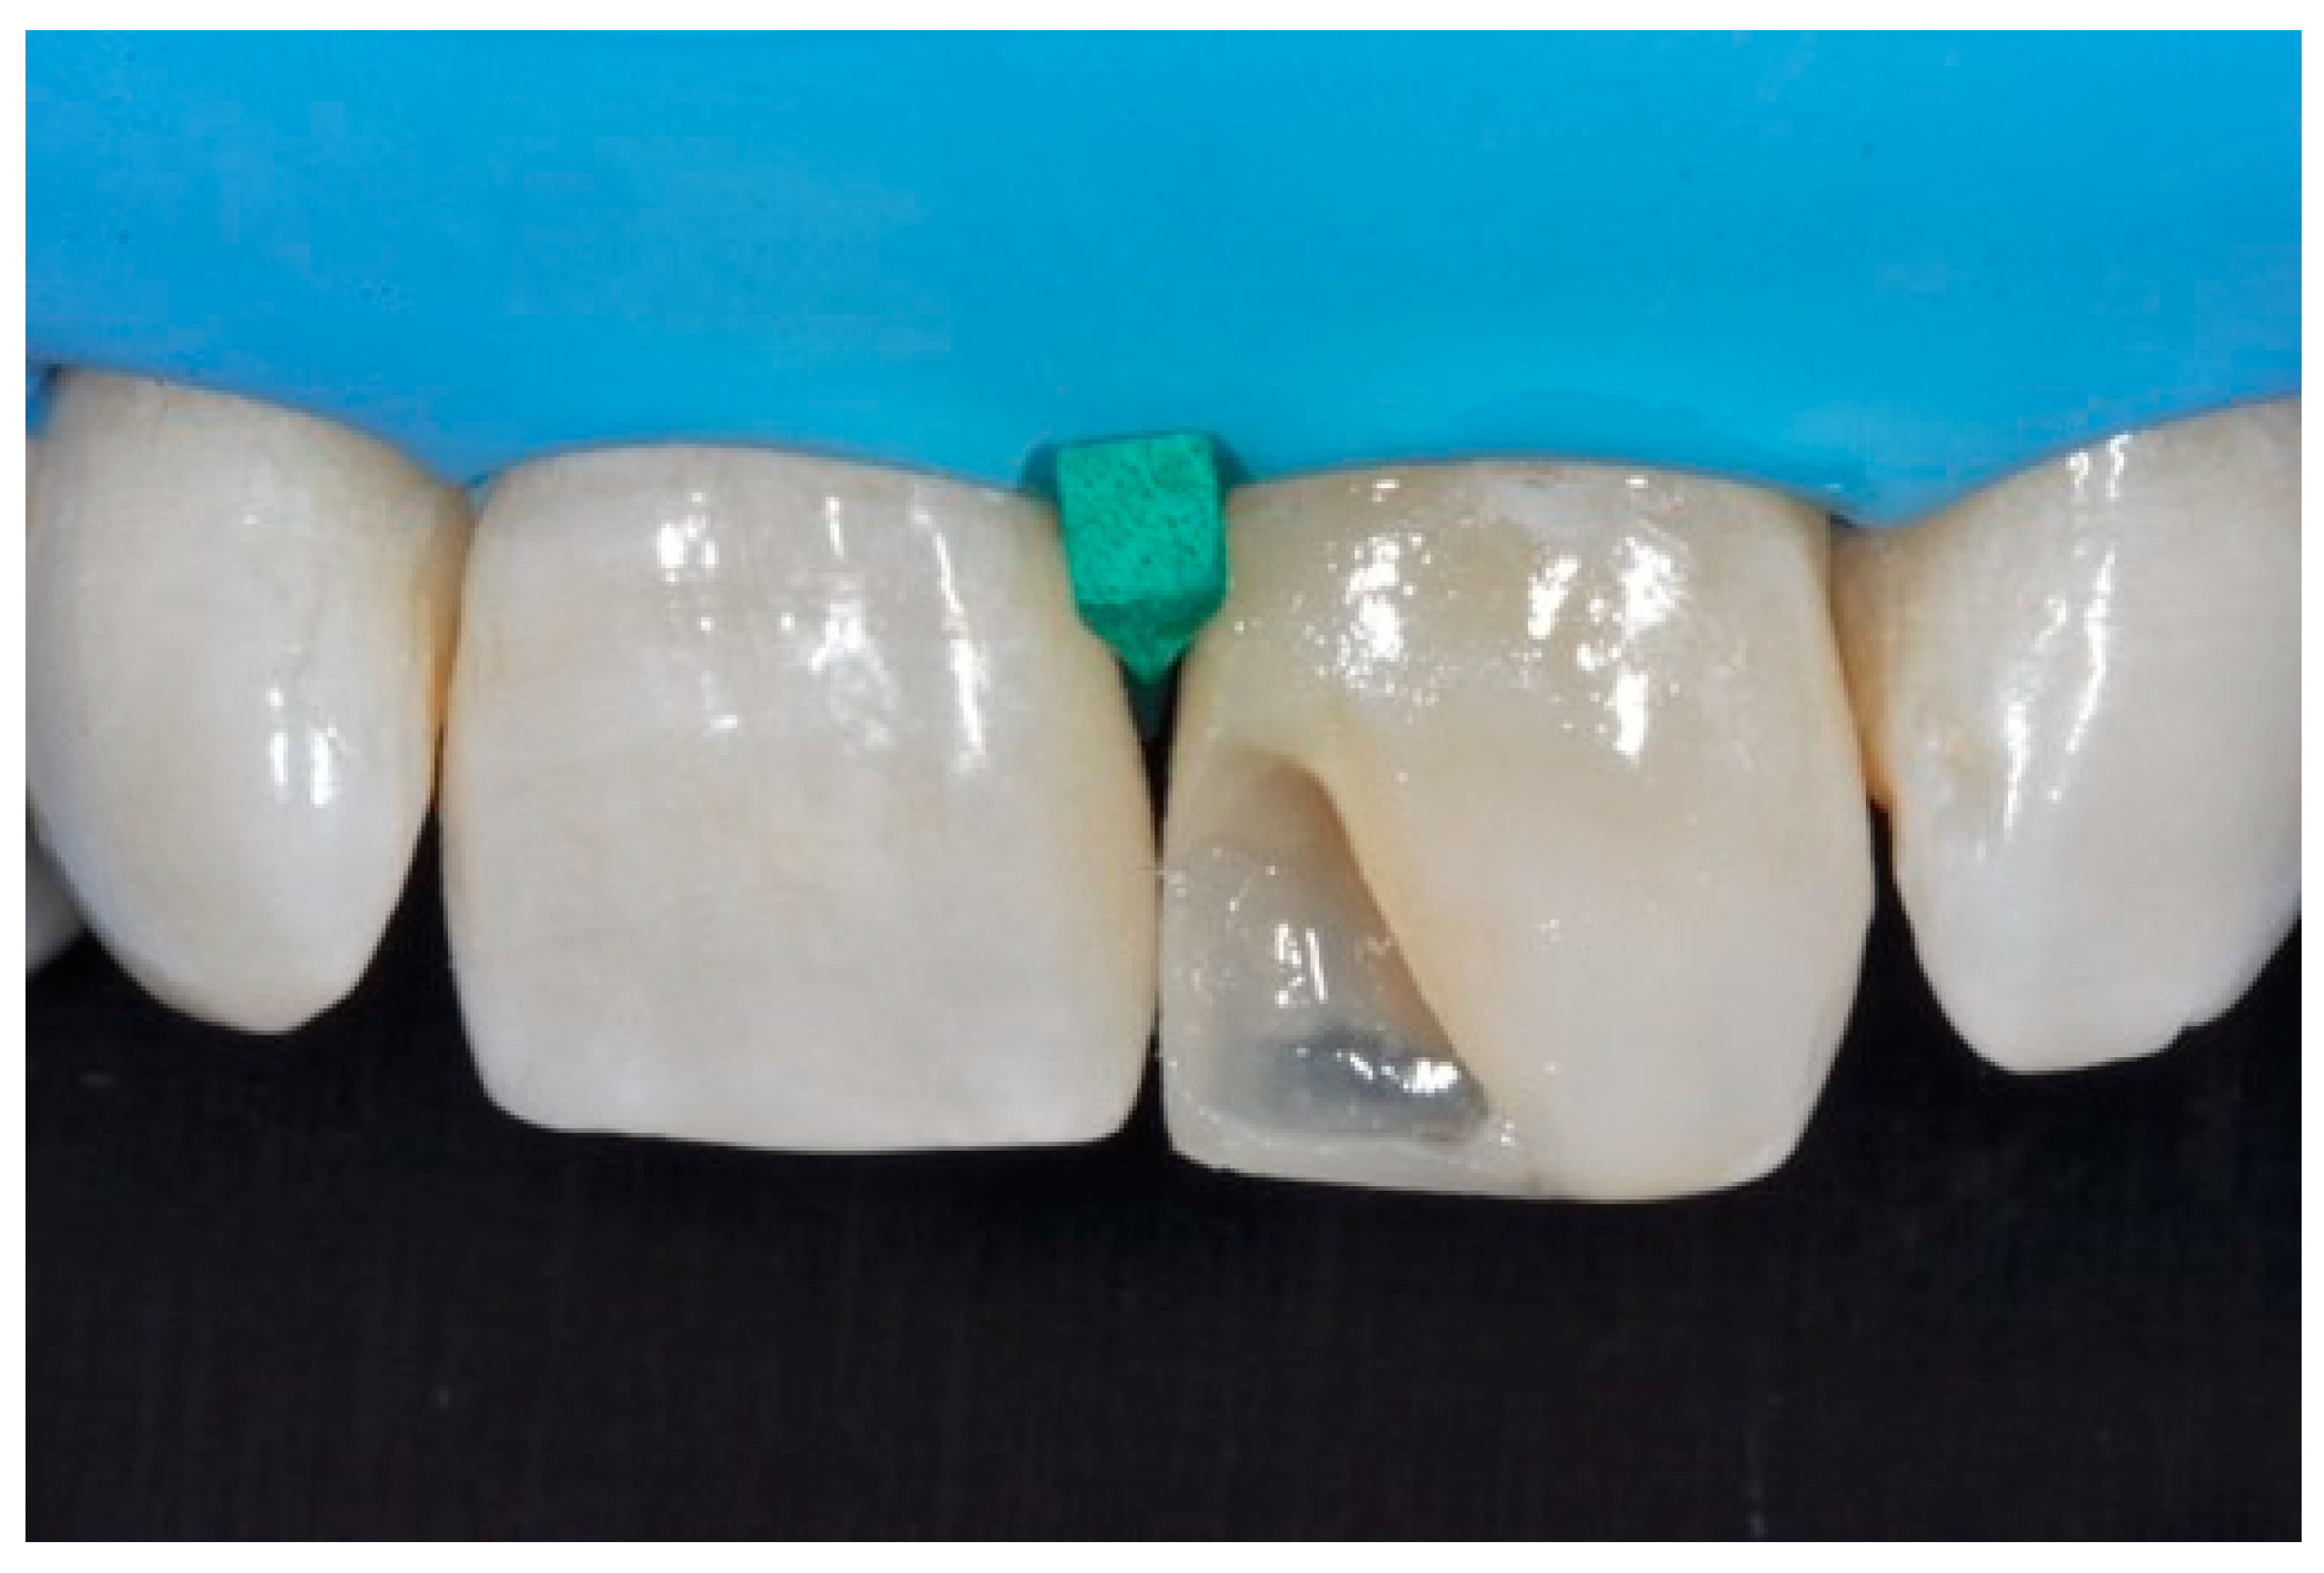

A healthy 38-year-old man referred to the dental office for the esthetic rehabilitation of left central maxillary incisor (Figure 41). Shade was selected as described in previous cases, using the button-try technique [14]. Isolation, preparation (Figure 42) and adhesive procedures were performed (Tokuyama Bond Force, Tokuyama Dental, Osaka, Japan). and Class III was restored on right central incisor (Asteria, A2B, Tokuyama Dental, Osaka, Japan). Frame was then completed on #2.1 (Figure 43) with the use of posterior sectional matrices using translucent and body material (Asteria, NE, A2B Tokuyama Dental, Osaka, Japan). After removing excesses both from the incisal margin and from the interproximal portion (Figure 44) silane and adhesive was applied strictly following the procedure described in Section 2.1.2. Dentinal body (Asteria, A2B, Tokuyama Dental, Osaka, Japan) was applied to reproduce internal anatomy (Figure 45) and then the external translucent enamel (Figure 46) (Asteria, NE, Tokuyama Dental, Osaka, Japan) was applied. The restoration shows good integration 6-months post-operative (Figure 47).

Figure 43.

The frame completed.

Figure 44.

The frame modified either in the incisal frame and in the interproximal wall.